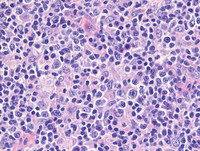

Sections from the tonsil shows unremarkable surface epithelium with underlying lymphoid tissue demonstrating destruction of architecture with prominent interfollicular expansion by large clusters and sheets of reactive histiocytes with intervening areas demonstrating plasma cells and occasional immunoblasts. The follicular structures are otherwise morphologically compatible with reactive secondary follicles.